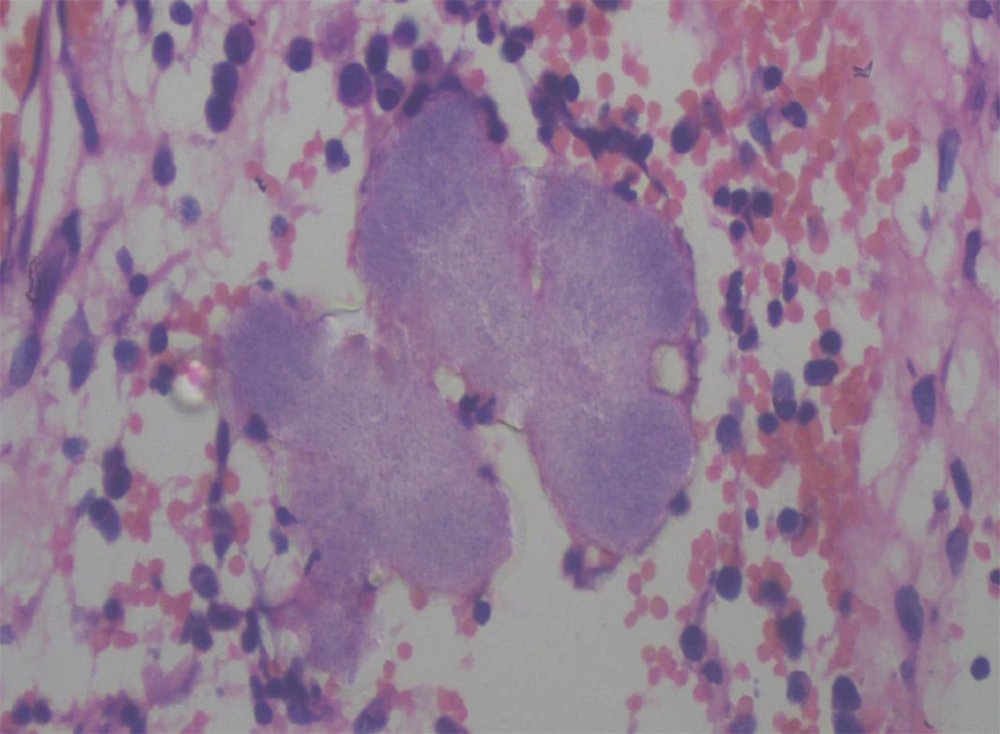

On histopathology, the subcutaneous tissue showed granulation with dense infiltration of lymphocytes, plasma cells, macrophages, and polymorphs, with a focal area of granulomatous reaction comprised of histiocytes and lymphocytes. Actinomycotic colonies showed multiple closely-packed granular, not easily discernible interlacing filaments with surrounding epithelioid cell granuloma (Figure 3).